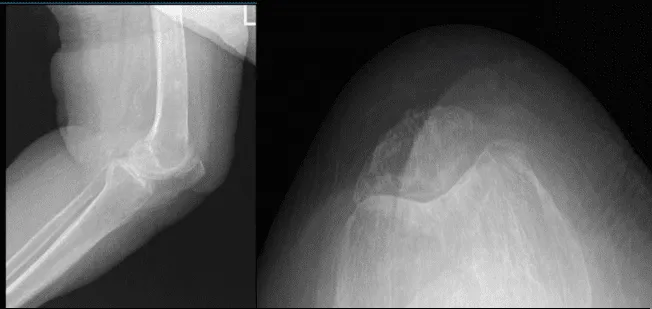

El paciente volvió a la consulta para el seguimiento postoperatorio. Presentó el resultado de su tomografía computarizada 4 semanas después de la operación y hay cambios degenerativos osteoartríticos leves.

Radiografía de rodilla izquierda con vistas oblicuas 3